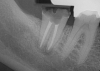

The patient returned for final evaluation of the provisional calcium-hydroxide endodontic therapy and resolution of the infection (33 days postoperatively). Fistula was not present; the tooth was not sensitive to percussion or mastication. The gold crown was removed using a high-speed metal cutting bur, the remaining caries were excavated conservatively, and the endodontic therapy was completed. Placement of glass-fiber reinforced composite and composite core buildup took place. The natural tooth structure to receive the glass-fiber post and a long-term restoration was available (Figure 8). Within one appointment, the tooth was restored (Figure 9). The patient was instructed to return for clinical and radiographic evaluation after 6 to 12 months to determine progression of periodontal healing. At that time, if the healing were adequate and the tooth were stable, evaluation of the tooth would be considered every 3 to 4 years.7

Fig 9. 33 days postoperative fiber-post placement and CAD crown.

Figure 9